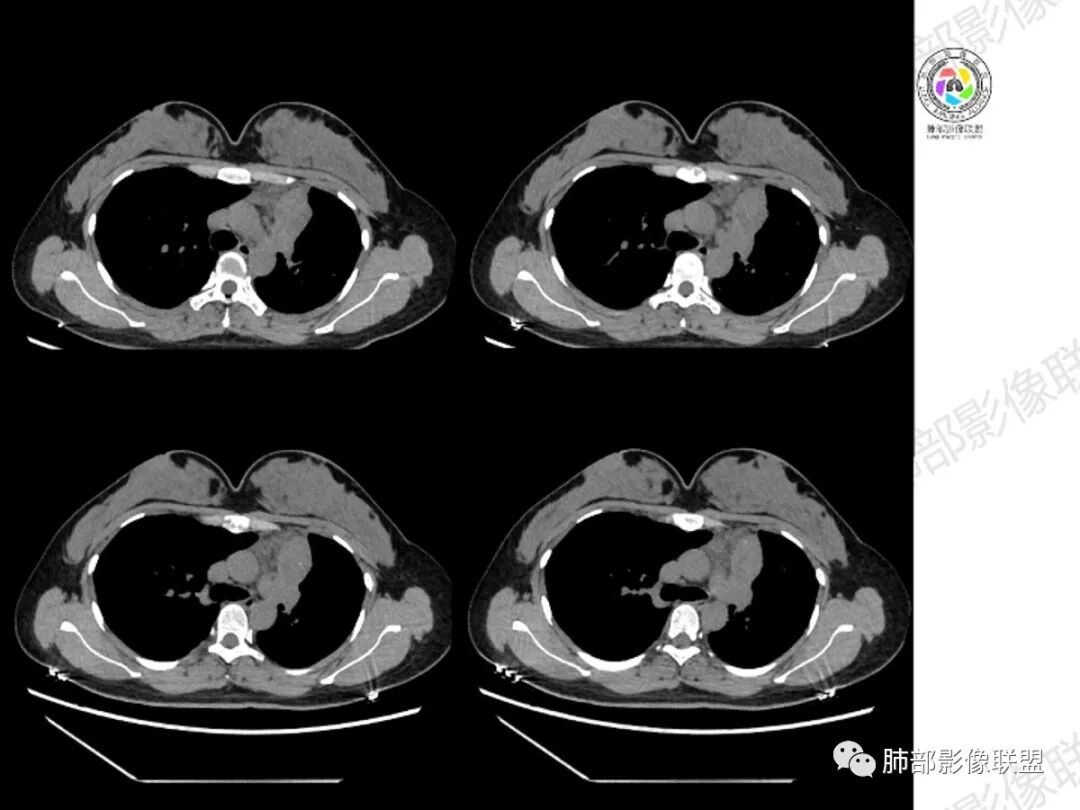

年轻女性,咳嗽咳痰一个月,左肺体积缩小,左肺尖部胸膜下实变影,宽基底与胸膜相贴,病灶边缘平直收缩,部分略膨隆,病灶下方可见支气管挤压,肺窗所示:周围伴有多发结节部分可见树丫征,纵隔窗可见病灶与纵隔胸膜黏连,部分与左肺动脉分界欠清,平扫密度尚均匀,增强扫描不均匀强化,内部可见多个低密度坏死,伴有条状血管影,纵隔淋巴结略有肿大。

胸部CT:左肺体积缩小,左肺上叶前段纵隔旁胸膜下大片实变影,边缘清楚、匀齐、平直收缩,部分略膨隆,周围多发结节、树芽卫星灶,纵隔窗病灶与纵隔胸膜黏连,实变内多发点状钙化。平扫密度尚均匀,增强扫描不均匀明显强化,多个低密度区,呈仙人掌样,伴有条状血管影,考虑慢性炎症伴左上叶前段支气管闭塞,TB?鉴别黏表、腺癌等。